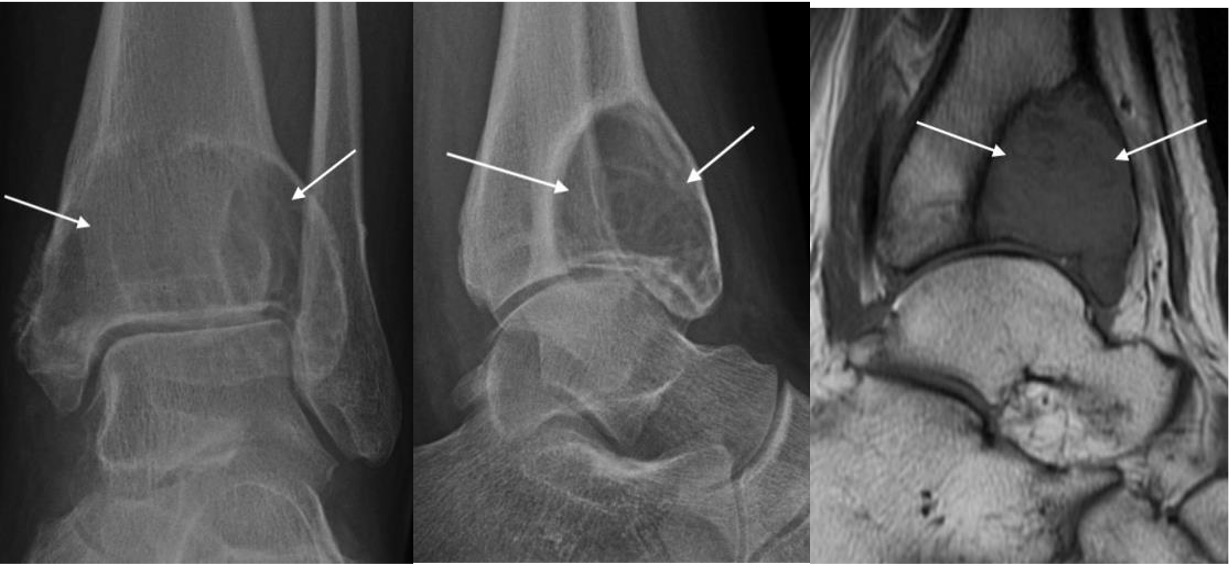

Giant cell tumour of bone

- Occur primarily in the mature skeleton

- Typical eccentric epiphyseal location, extending to subarticular surface

- Seen as radiolucent lesion with well-defined, but non-sclerotic, margin

- May be expansile with cortical thinning

- Approximately 15% of giant cell tumours are malignant

Giant cell tumour of distal tibia seen as eccentric expansile epiphyseal lucent lesion (arrows)